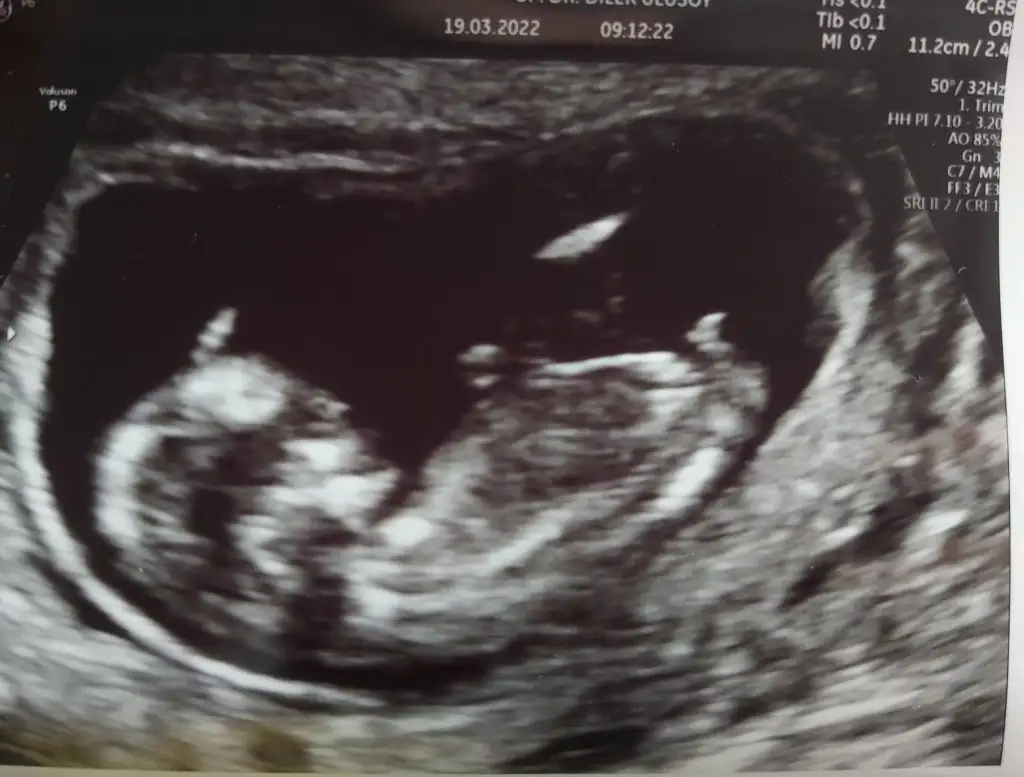

Kızlar bugün kontrolüm vardı herşey yolundaymış çok şükür ense kalınlığı burnu hepsi normal çıktı. Herkesinkine bir yorumum oluyordu kendi bebeminkine bişey diyemiyorum Doktor erkeğe benzettim ama kızlarda da oluyor çıkıntı 16.haftada net söylerim dedi.

Eklentiler

• 20220319_094104.webp

30,1 KB · Görüntüleme: 72

• 20220319_094929.webp

36,8 KB · Görüntüleme: 73